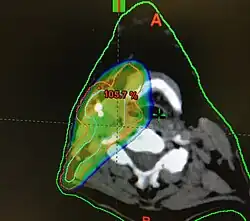

Radiotherapy

Concerns over the morbidity associated with traditional open surgical en-bloc resection led to exploring alternative approaches using radiation.[122] Intensity-modulated radiation therapy (IMRT) can provide good control of primary tumours while preserving excellent control rates, with reduced toxicity to salivary and pharyngeal structures relative to earlier technology. HPV+OPC has shown increased sensitivity to radiation with more rapid regression, compared to HPV-OPC.[133] Generally, radiation can safely be delivered to the involved side alone (ipsilateral), due to the low rate of recurrent cancer on the opposite side (contralateral), and significantly less toxicity compared to bilateral treatment.[e][135][134] IMRT has a two-year disease-free survival between 82 and 90%, and a two-year disease-specific survival up to 97% for stage I and II.[136][137]

Dosimetry

The probability of xerostomia at one year increases by 5% for every 1 Gy increase in dose to the parotid gland. Doses above 25–30 Gy are associated with moderate to severe xerostomia. Similar considerations apply to the submandibular gland. Xerostomia is less common if only one parotid gland is included in the radiated field[146] and the contralateral submandibular gland is spared (less than 39 Gy)[147] In the same manner, the radiation dose to the pharyngeal constrictor muscles, larynx, and cricopharyngeal inlet determine the risk of dysphagia (and hence the dependence on gastrostomy tube feeds). The threshold for this toxicity is volume-dependent at 55–60 Gy,[148][149][150][91] with moderate to severe impairment of swallowing, including aspiration, stricture and feeding tube dependence above a mean dose of 47 Gy, with a recommended dose to the inferior constrictor of less than 41 Gy.[151][152] Dose-toxicity relationships for the superior and middle constrictors are steep, with a 20% increase in the probability of dysphagia for each 10 Gy.[153] For late dysphagia, threshold mean total constrictor doses, to limit rates of greater than or equal to grade 2 and 3 below 5% were 58 and 61 Gy respectively. For grade 2 dysphagia, the rate increased by 3.4% per Gy.[154] Doses above 30 Gy to the thyroid are associated with moderate to severe hypothyroidism.[155] Subjective, patient-reported outcomes of quality of life also correlate with radiation dose received.[143]